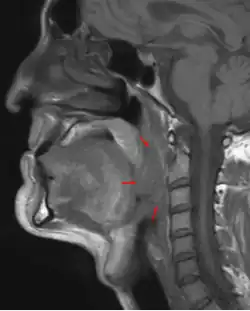

Oropharynxkarzinome können häufig schon durch eine Spiegeluntersuchung diagnostiziert werden. In aller Regel erfolgt zusätzlich eine Panendoskopie des gesamten Rachenraums mit Intubationsnarkose. Dem Patienten werden dabei per Biopsie kleine Gewebeproben entnommen, die zur Absicherung der Diagnose feingeweblich untersucht werden.

Für das Tumorstaging und die Therapieplanung werden bildgebende Verfahren, wie Sonographie (Ultraschall), Computertomographie (CT) oder Magnetresonanztomographie (MRT), eingesetzt. Während die Sonographie einen guten Überblick über einen eventuellen Befall der Lymphknoten verschafft, können mit den beiden anderen bildgebenden Verfahren auch die Tumorausdehnung in die Tiefe bestimmt und eine Infiltration weiterer Strukturen wie z. B. der Halsgefäße beurteilt werden. Zur Untersuchung auf Fernmetastasen wird in der Regel eine Röntgen- oder CT-Aufnahme der Lunge sowie eine Ultraschalluntersuchung der Leber erfolgen. Zum Ausschluss von Tochtergeschwülsten im Knochen kann eine Szintigraphie erfolgen.[14]